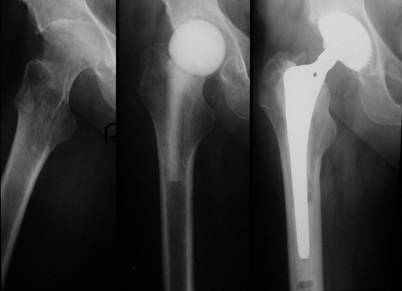

After demonstration of the spacer via the transgluteal approach, spacer removal, debridement and pulsatile lavage, we could implant a standard prosthesis type Aesculap Bicontact with a screw cup type SC (Fa. Aesculap, Tuttlingen, Germany) in 7 cases (Fig. 1). In one case a Link-revision stem (Fa. Waldemar Link, Hamburg, Germany) was implanted, whereas the acetabular cup was also a screw cup SC.

Fig 1

Left: Destructive bacterial coxitis; Middle: Spacer implantation between stages; Right: 3 months later and after infection eradication, a prosthesis implantation (SC® cup, Bicontact® stem, Fa. Aesculap, Tuttlingen, Germany) has been performed.